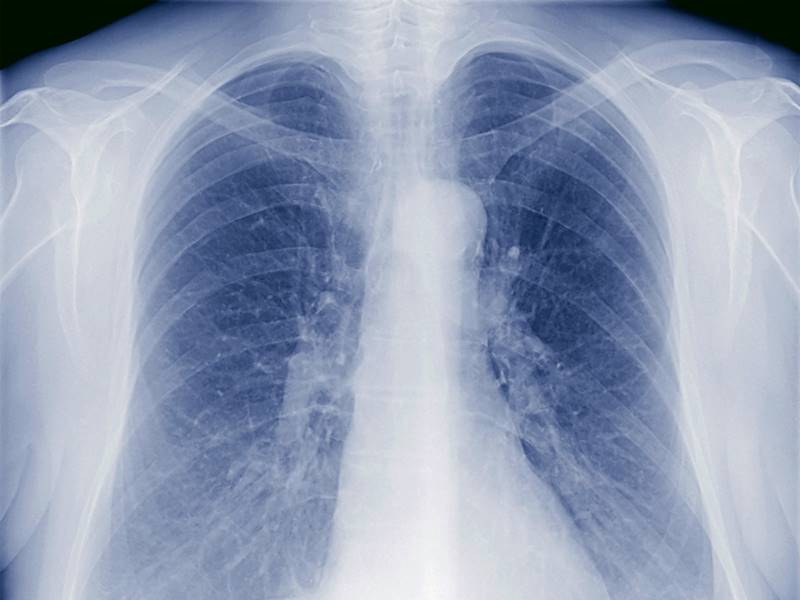

A tuberculose é uma doença infecciosa causada pela bactéria Mycobacterium tuberculosis, também conhecida como bacilo de Koch. Ela geralmente afeta os pulmões, mas pode se espalhar para outras partes do corpo, como ossos, rins e sistema nervoso central. Continua depois da publicidade

Diagnóstico

No Brasil, o diagnóstico da tuberculose é realizado conforme preconizado no Manual de Recomendações Para o Controle da Tuberculose no Brasil, sendo subdividido em diagnóstico clínico, diferencial, bacteriológico, imagem, histopatológico e por outros testes diagnósticos.